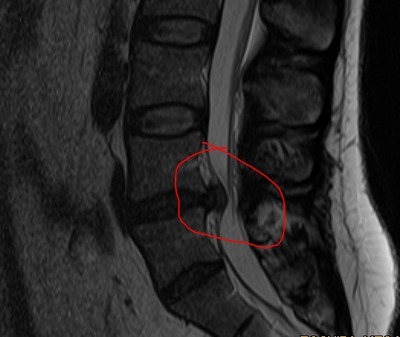

Поясничная грыжа, ходить не могу, стоять тоже, лежать больно. Невролог (пигалица в кроссовках) говорит: милый человек, позвоночник болеть не может - это ж кость. Болят мышцы, которые в гипертонусе. Они не работают полноценно, что приводит к сдавливаниям и смещениям. Вы сидите много, а это статическая нагрузка. Надо давать мышцам работать.